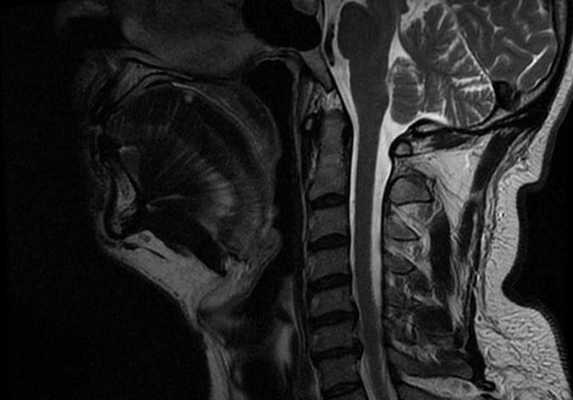

Особенностью МРТ являлась высокая контрастность мягких тканей. Плотные костные ткани или зубоврачебный материал не создавали артефактов, что давало возможность получать четкое изображение опухоли полости рта, определять распространение в мягкие ткани, глубокие отделы орофарингеальной зоны, в область неба. На Т1-ВИ все опухоли имели ту же интенсивность сигнала, как у окружающих мышц или слабее (рис.7).

Рис.7. Пациент С., 55 лет. МРТ ротоглотки в сагиттальной проекции в режиме Т1-ВИ. Опухоль дна полости рта с переходом на нижнюю поверхность языка (стрелки)

После введения контрастного вещества все опухоли показывали усиление сигнала. При локализации опухолевого процесса в области языка (12 пациентов) границы опухоли визуализировались более четко. В режиме Т2-ВИ опухолевые узлы проявлялись более высокой интенсивностью сигнала, чем у окружающих мышц (рис. 8).

Сложно было с помощью МРТ визуализировать опухоли любых размеров с поверхностным распространением, не выходящие за пределы слизистой оболочки. Опухоли малых размеров (Т1 стадия) в 2 наблюдениях были однородны, не имели центральной зоны некроза и сливались с мышцами. С увеличением размера опухолевого узла отмечалась неоднородность структуры. В наших исследованиях удалось выявить небольшие опухоли Т1 и Т2 стадий, локализованные в области языка и дна полости рта. В 9 наблюдениях опухоли Т2 стадии, не накапливающие контраст при МСКТ исследовании, хорошо визуализировались при МРТ в режимах Т2-ВИ, STIR, проявляясь сигналом высокой интенсивности. Можно было четко видеть границы опухоли и оценить ее размеры (рис. 9,10).

Рис. 8. Пациент П., 76 лет. МРТ полости рта в сагиттальной проекции в режиме Т2-ВИ. Опухоль языка, высокая интенсивность сигнала на фоне окружающих мышц (стрелки)

Рис. 9. Пациент А., 66 лет. МРТ дна полости рта в сагиттальной проекции в режиме Т2-ВИ. Опухоль дна полости рта размерами 2,0х1,8 см с распространением на основание языка Т1N0M0 (стрелки). Границы опухоли четко визуализируются, структура однородная

Не возникало сложностей в выявлении опухолевых узлов Т3, Т4 стадий, имевших все отмеченные выше признаки в различных сочетаниях в 36 исследованиях (рис. 11). Из 50 обследованных с помощью МСКТ и МРТ пациентов у 26 (52,0%) были выявлены метастазы в лимфатических узлах шеи. Поражались преимущественно лимфатические узлы I-II уровня. Признаками метастаза плоскоклеточного рака в лимфатических узлах были: увеличение размера лимфатического узла более 1,0 см, изменение формы лимфатического узла с бобовидной на округлую, структурные нарушения в узле, нечеткость наружных контуров узла, уплотнение окружающей жировой ткани на КТ или изменение сигнала на МРТ.